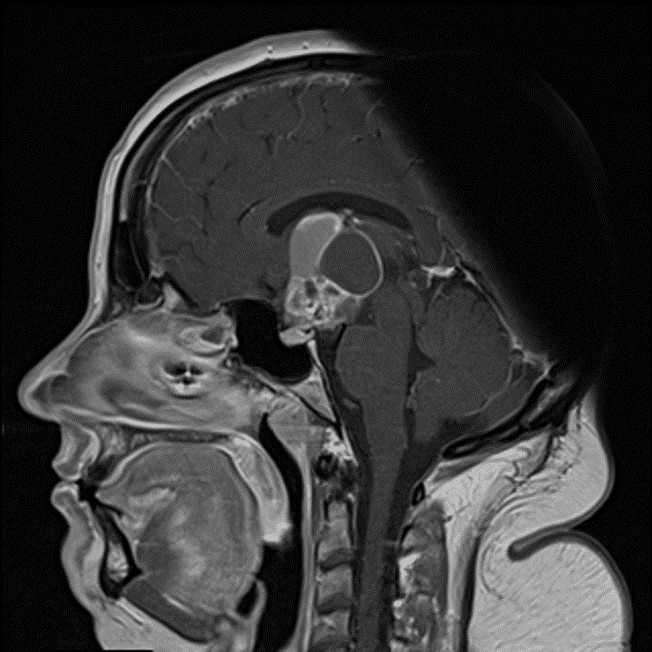

- Mixed cystic and solid suprasellar mass measuring 3.5 x 2.3 x 4.2 cm with solid enhancement of the solid components and peripheral enhancement of the cystic components

- The mass contacts and anteriorly displaces the optic chiasm and splays the optic tracts

- The pituitary gland is seen separate from the mass

Solid enhancement of the solid components and peripheral enhancement of the cystic components.